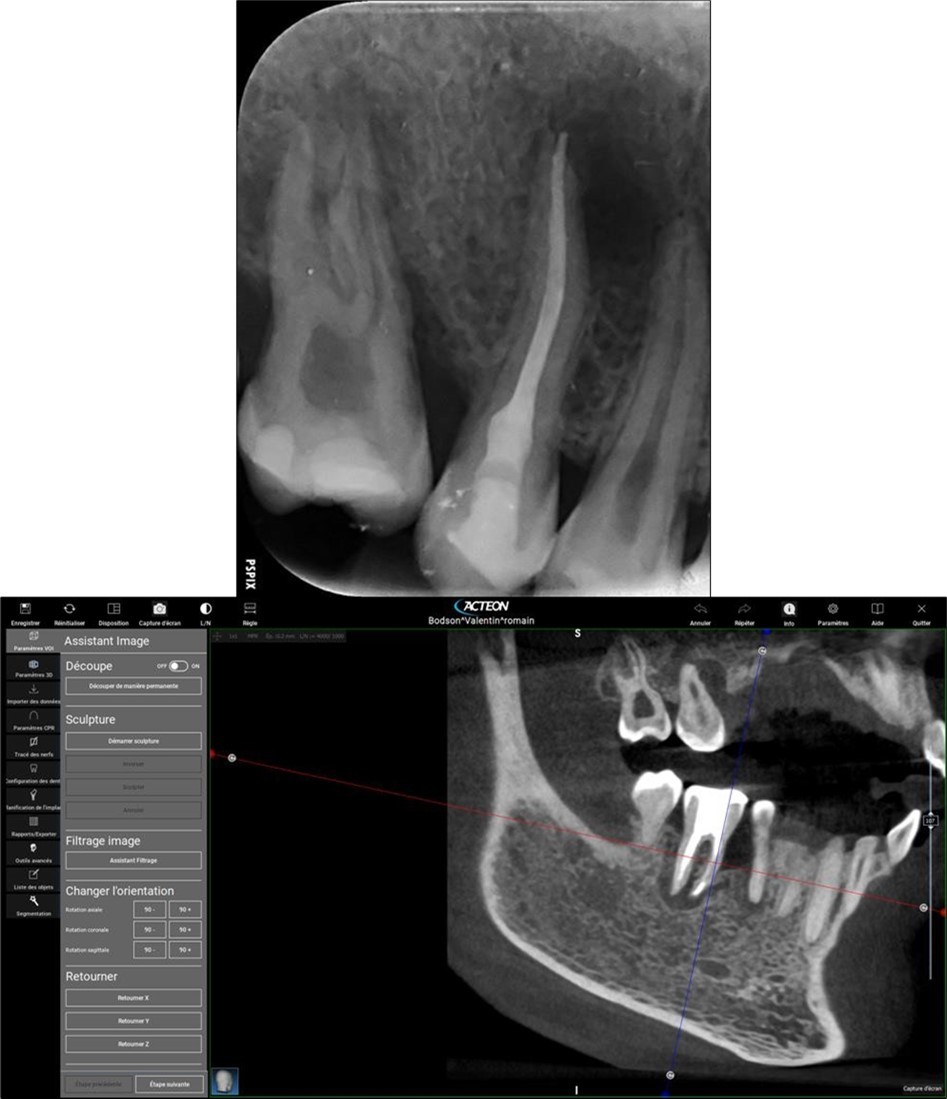

3. Endodontic root canal treatment and retreatment were performed on teeth 14, 15, 16, 25, 26, 35, 36, and 46 using a K manual file 10/30/40/50/60/70 (Dentsply-Maillefer). Hyflex Edm (Coltene) 25/06 was used for the preparation of the canals, which were irrigated with 3% sodium hypochlorite and 17% ethylenediaminetetraacetic acid. Gutta-percha were calibrated to the diameter of the root apex constriction and obturation was conducted using Endosequence Bc Sealer (Brasseler) 15.

Complete healing of periapical lesions and treatment of teeth 26 and 16 with advanced endo-perio lesions posed challenges due to the patient’s delayed supplementation. In this case, surgical endodontic procedures and the extraction of teeth with advanced endo-perio lesions were considered risky because of the underlying metabolic healing impairment. Figure 3

Figure 3.6. 7, 8, 9, and 10 showing postoperative periapical radiographs of these endodontic treatments.